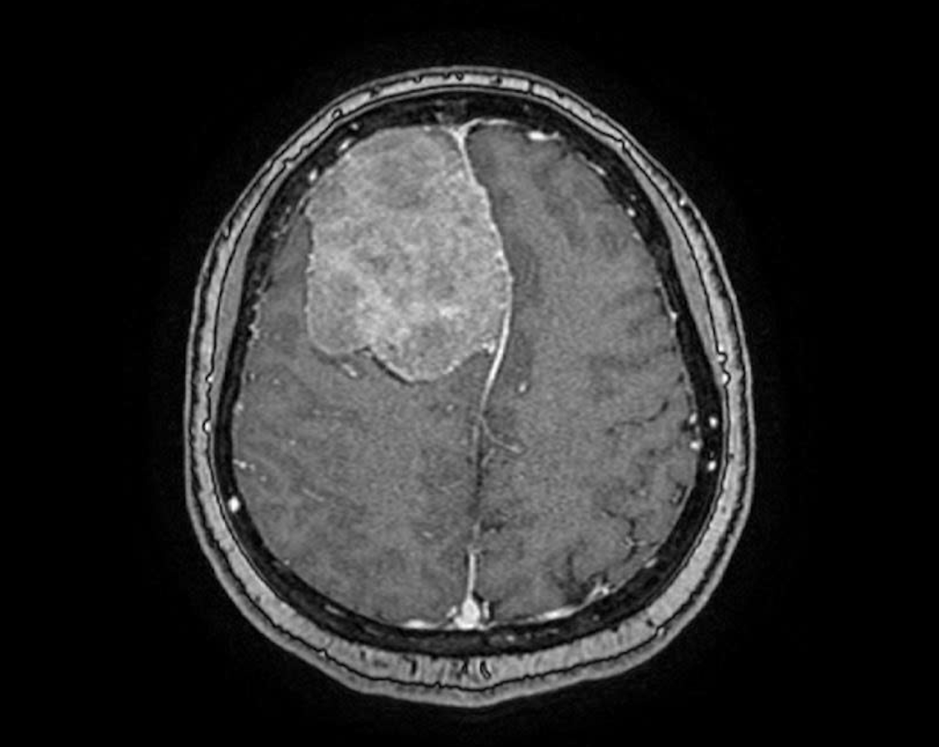

Chị Trịnh Nhật Khánh (45 tuổi, TP.HCM) là một võ sư đã gắn bó nhiều năm với bộ môn võ cổ truyền. Thời gian gần đây, chị thỉnh thoảng bị đau đầu nhẹ nên đi tầm soát đột quỵ tại Bệnh viện FV. Kết quả chụp cộng hưởng từ (MRI) khiến chị và cả gia đình không khỏi sốc: một khối u màng não khổng lồ, đường kính hơn 6cm đang âm thầm chiếm gần ¼ thể tích bán cầu não phải.

Phim chụp MRI cho thấy một khối u lớn như trái cam sành trong não phải bệnh nhân